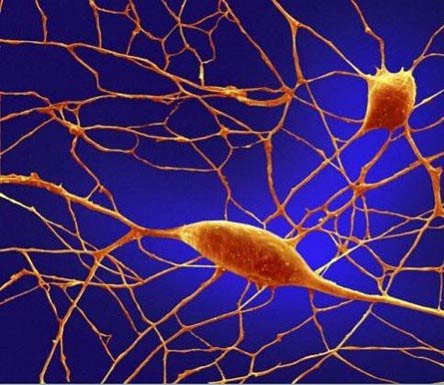

متفاوتترین سلول نرون است نرون دارای ابعاد و شکل خاصی است و طول آن از سایر بقیه سلولها درازتر و طولانی تر است که به 3 فوت می رسد.

نرونها دارای زیباترین اشکال و رنگها هستند و بیشترین عملکرد را در بین سایر سلولها دارا هستند.

سلولهای مغز

نورونهای مغز